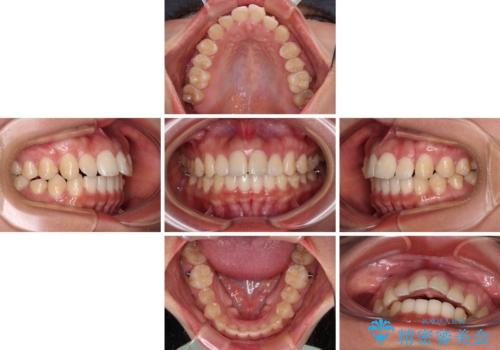

- 前歯の突出感を気にして来院された患者様です。

奥歯の咬み合わせは理想的な咬合に近く、インビザラインでも十分に対応できる歯列でした。

舌の突出癖を改善するためのトレーニングを行いつつ、上下歯列全体を後方に移動させ、更にはIPR(歯と歯の間を削る)によりスペースを獲得することで、口元の突出感を改善することとしました。

治療途中に上顎前歯が歯髄壊死を起こし、変色してしまいました。

痛みを感じたらすぐに連絡いただくよう伝えていましたが、忘れてしまっており、痛みと変色が発現したことで、すぐに連絡することを思い出されたとのことでした。

今後は、根管治療を行った後に、オールセラミッククラウンにて補綴治療を行う予定です。